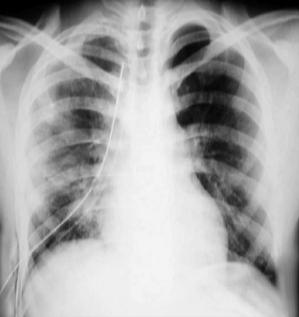

Radiología Pos - operatoria

Radiología Pos - operatorio mediato:

Pulmón dercho expandido, ventilado.

Persiste uno de los tubos torácicos a sello de agua, al 8° día por drenaje serohemático en el sistema.

La radiopacidad del hemitórax, requiere de varios meses para desaparecer.